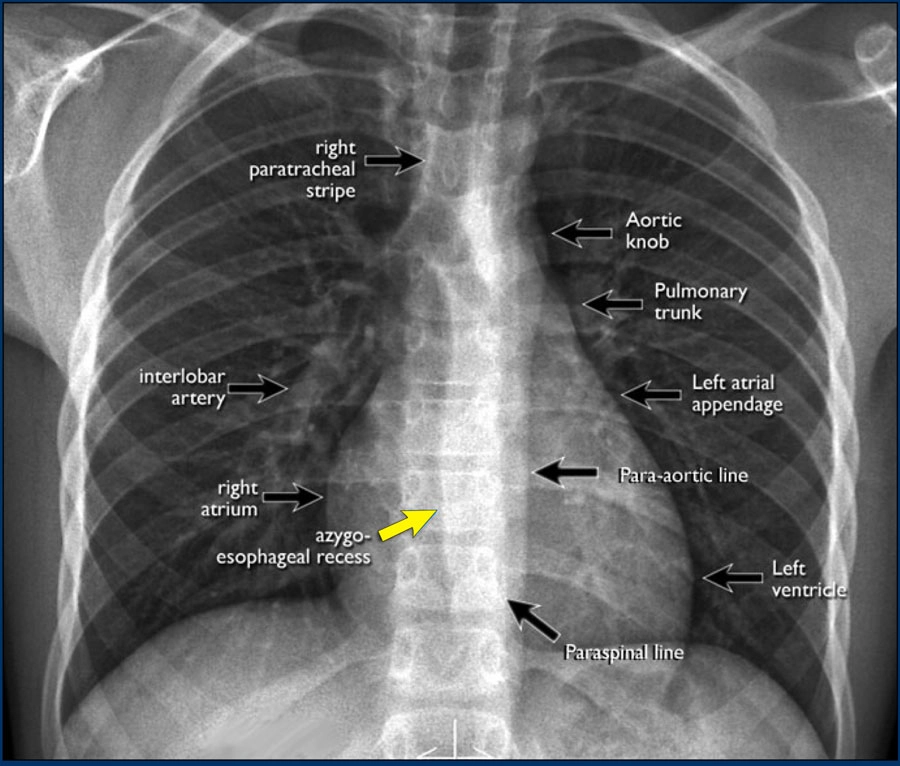

• Dấu hiệu và hình ảnh

• Hình ảnh